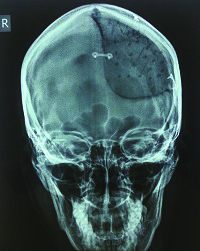

A 23-year-old woman presented at the University Hospital Osijek, Croatia, department of neurosurgery, with a benign change in the bones of her skull. The deformed part of the skull was on her forehead, and highly visible. In addition to needing to remove part of the diseased bone, doctors determined that it was also necessary to address the woman’s cosmetic defects in order to reduce the psychological consequences of the surgery.

Traditionally, this procedure, a cranioplasty, required surgeons to tailor polymethyl-methacrylate (PMMA) bone cement implants to the patient’s skull using silicone molds. But these molds often have poor aesthetic results, long production times and high costs. Additionally, the operation would be lengthy and the final outcome was not guaranteed.

Before 3D printing, the surgeon had to shape the bone cement implant by hand. The aesthetic results were poor, the operation lasted longer and the outcome was less sure. With 3D printing, the outcome is much better because the implant is tailored to an individual’s CT scan.

A 23-year old woman’s successful cranioplasty using 3D printing technology.

Cranial surgeries such as this woman’s, require high precision and accuracy of the implant as well as compactness of the material in order to ensure successful sterilization of the mold. 3D prototyping models enable the hospital to remove any faults in the mold design in the early phases, before surgery.

“3D printing enables faster product development and easier communication with patients. This aids in early detection of faults and problems which makes the whole process faster and more economical,” said Sercer. The first step is converting a patient’s CT scan into a virtual 3D image. This prototype is 3D printed to check for an exact fit of the implant by measuring it against the bone cavity in the patient’s skull. Only once the exact measurements are confirmed is the mold filled with a low-viscosity PMMA, or bone cement, to create the actual prosthesis.